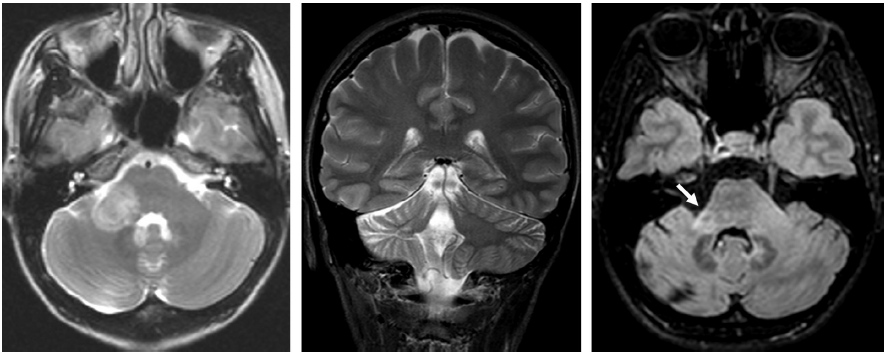

在成人中,泛小脑萎缩是在MRI上观察到的最常见的影像表现。图3显示的是由于副肿瘤性小脑综合征导致的小脑萎缩。该患者有亚急性小脑综合征病史,随后发现恶性胸腺瘤

。

图3 副肿瘤性小脑综合征相关的广泛小脑萎缩。左:头颅MRI T2加权序列冠状位图像。右:头颅MRI T1加权序列矢状位图像。

图4显示的是全身免疫疾病相关的小脑萎缩。特异的影像学征象,如T2加权图像中脑干周围的低信号边缘,见于表面铁沉积症(图 5)。

图 4 自身免疫性多内分泌腺综合征相关的小脑萎缩。左:头颅MRI T1加权序列矢状位影像显示蚓部萎缩。右:头颅MRI T2加权序列冠状位图像显示小脑沟增大。

图 5 表面铁沉积症患者表现为小脑性共济失调。头颅MRI T2加权序列图像显示中脑低信号边缘(箭头)。

切除原发性肿瘤后,不可逆的小脑后遗症很常见,结构成像可清楚地显示其程度(图 6)。

图 6 手术切除室管膜瘤后小脑和脑干的后遗症。图为头颅MRI T1加权序列图像。